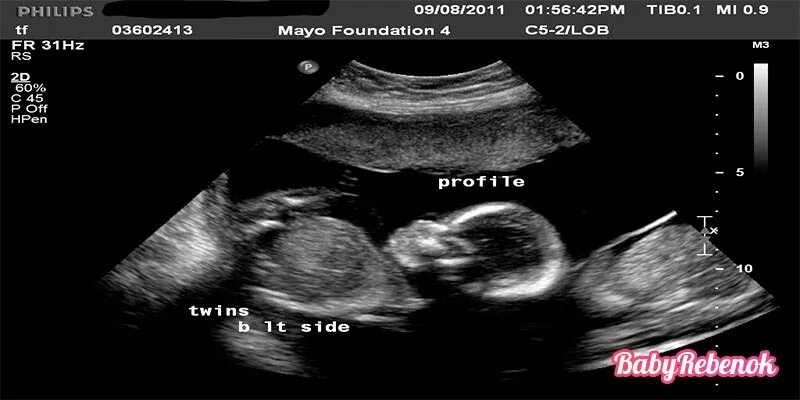

29 недель 4 дня